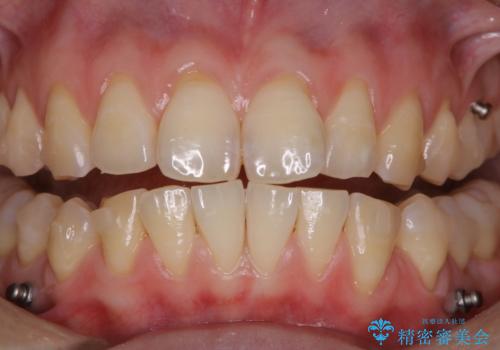

インビザライン矯正治療中のPMTC

インビザラインでの治療中の患者様のクリーニング前後写真です。

- インビザライン矯正中に茶色が気になるとのことで来院されました。PMTC30分コースを行いました。

矯正治療中は虫歯や歯周病リスクが高くなります。